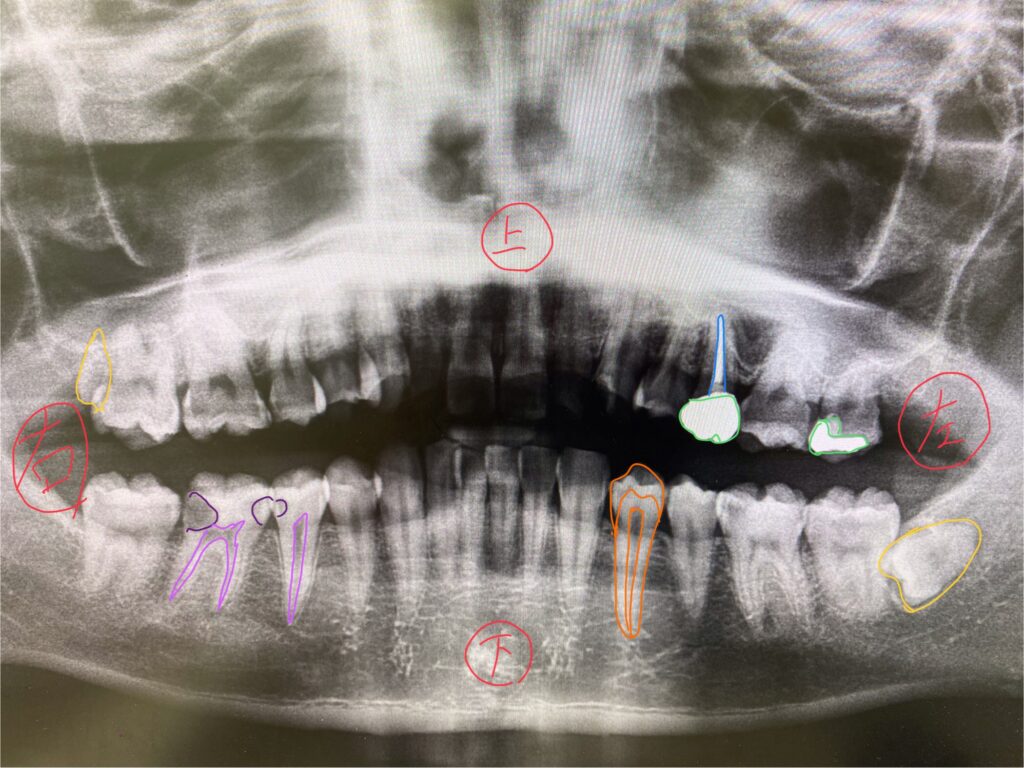

上記にレントゲンを載せておりますが、まず画面の右側はお口の中の左側。画面の左側がお口の中の右側です。

ややこしいですよね笑。以下色毎に解説していきます。

オレンジ

こちらは健康な歯の構造です。外側からエナメル質。象牙質。神経。の三層構造です。

エナメル質は人体で一番硬い部分で、虫歯の進行はゆっくりです。象牙質に虫歯が入り込むと大きく広がり、進行が早くなります。神経に近付くと痛みを感じるようになり、神経を取る治療になる可能性が高くなります。

みどり

こちらは銀歯、ジルコニア、樹脂などの人工物です。人工物はレントゲンでは白く写ります。

みずいろ

こちらは神経をとっている歯になります。中にお薬が詰まっているため白く写っています。

むらさき

こちらは虫歯になります。虫歯はレントゲンだと黒く写ってきます。虫歯の好発部位は、歯の隣接面(接触してる部分)、咬合面(噛む面)。ここを中心に見て虫歯のチェックをします。

きいろ

こちらは親知らずです。この方は埋まっており、横向きに生えています。

このようにレントゲンにはいろいろな情報が詰まっています。